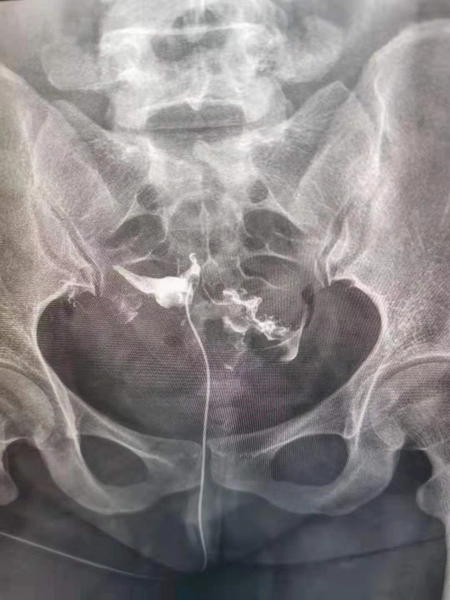

女性不孕中,子宮輸卵管因素導致的不孕約占50%,輸卵管在受孕的過程中具有重要地位,精子和卵子在輸卵管壺腹部相遇形成受精卵,然后依靠輸卵管的蠕動和管腔內纖毛的擺動將受精卵送回宮腔,而胚胎的著床、胎兒的孕育都是在子宮內完成。因此檢查子宮及輸卵管狀態是不孕癥診治的重要步驟。

1.造影成像的圖像質量清晰直觀,臨床醫生可以通過讀片來判斷子宮輸卵管腔內的狀態,清晰的圖片對于炎癥、積水等異常診斷更為準確,降低了漏診率和誤診率,對下一步不孕癥的處理方向提高幫助。